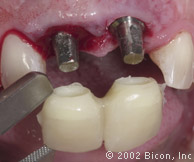

Вид спустя десять недель после установки имплантантов

Установка двух 3.0mm Impression Post

Снятие слепка и подбор цвета

Установка временной и изготовление постоянной конструкции